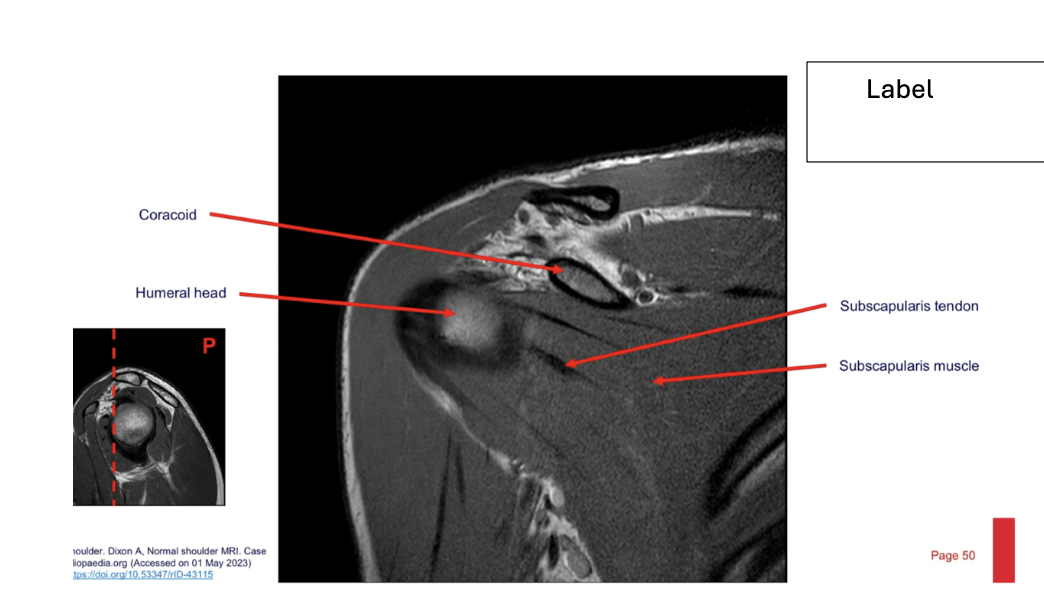

label each

2- lateral and medial condyles of femur

4- vastus lateralis muscle

5-posterior cruciate ligament

6- anterior cruciate ligament

7- medial meniscus of knee

8- lateral meniscus of knee

9-tibia

10-fibula